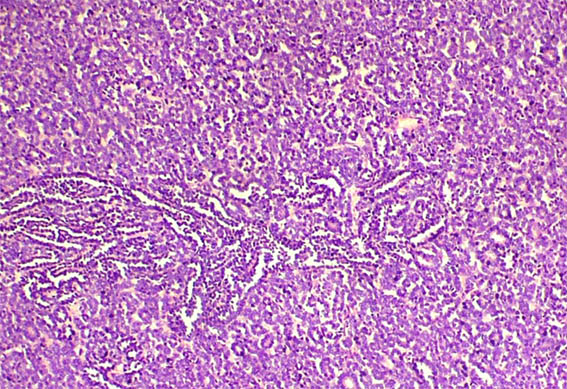

Figura 1.

H&E, X100.